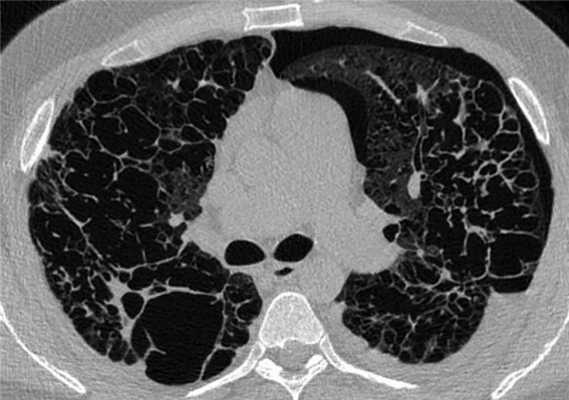

Рентгенологическая картина гистиоцитоза легких меняется в зависимости от стадии развития заболевания. Наиболее информативным рентгенологическим методом исследования при ЛКГЛ является компьютерная томография высокого разрешения (КТВР). На ранних стадиях заболевания при выполнении КТВР выявляют мелкие (3-6 мм, реже до 1 см) симметричные узелки в верхних и средних отделах легких, по мере прогрессирования заболевания появляются полости (рис. 1) Рисунок 1. КТ легких. Множественные симметричные узелки и полости в верхних отделах легких. , число которых со временем нарастает при одновременном регрессе узелков [7]. При длительном течении заболевания определяются множественные полости и участки «сотового легкого» (рис. 2) Рисунок 2. КТ легких. Множественные полости и участки «сотового легкого». . Для гистиоцитоза легких, в отличие от других интерстициальных заболеваний легких, патогномонично симметричное поражение верхних и средних отделов легких, поражение нижних отделов легких имеет место при тяжелом течении заболевания. Гистиоцитоз у взрослых чаще протекает в форме изолированного поражения легких, однако в 15% наблюдений имеет место поражение костей скелета, реже лимфатических узлов, кожи и других органов [8].